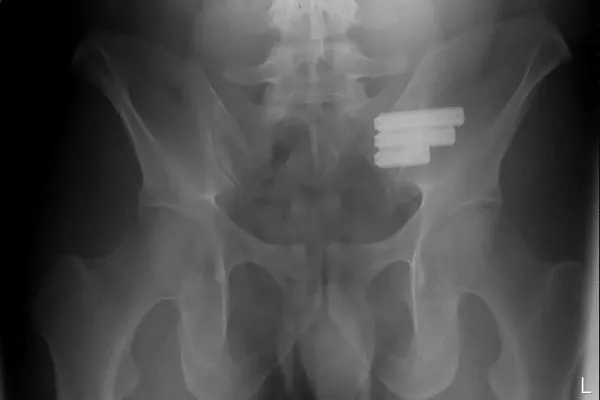

- 微創手術過程中醫生會在患者臀部切一個2-3公分的小切口進入關節的位置,並在即時的X光成像下進行手術流程,植入薦髂關節螺釘(Sacroiliac screws)將關節固定並融合來增強穩定性。手術所需時間大約1個小時,患者在術後1-2天就可以出院回家。

- 開放式手術會在臀部側面切一個15-20公分的切口,進入到薦髂關節去除關節中的軟骨,並使用薦髂關節螺釘進行固定融合。手術所需時間大約3個小時,患者住院時間可能需長達5天左右。